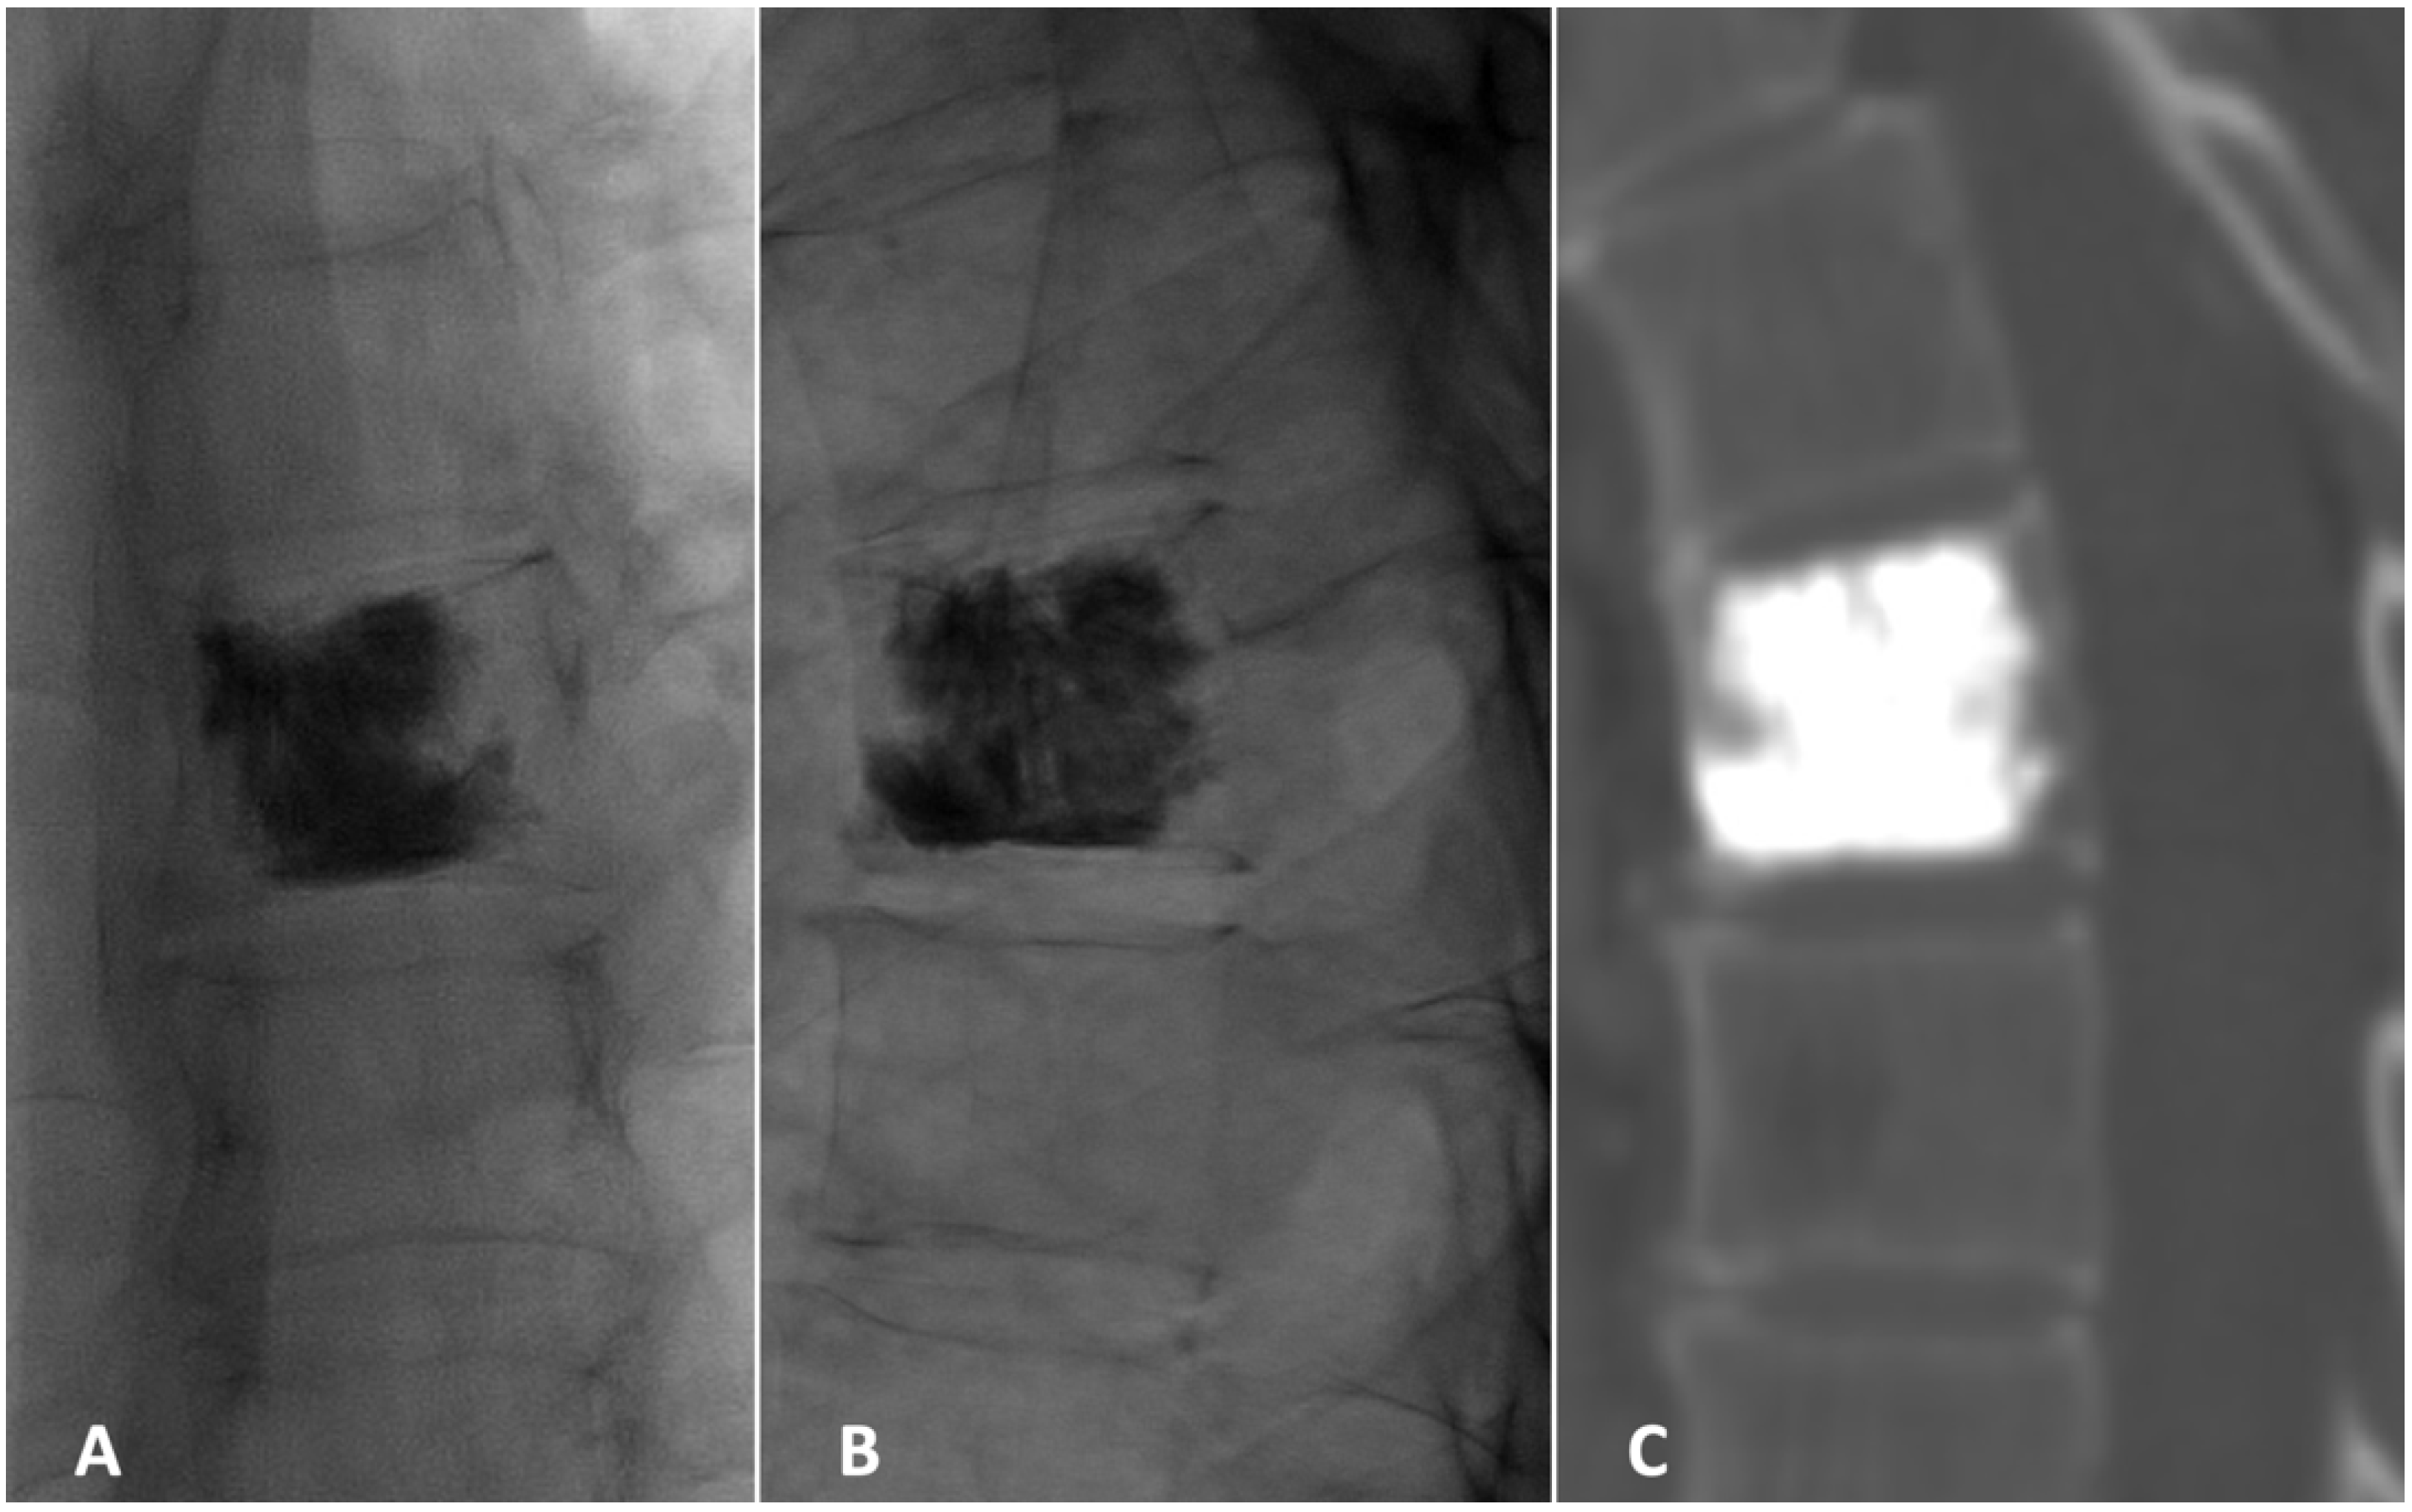

2. Case Presentation